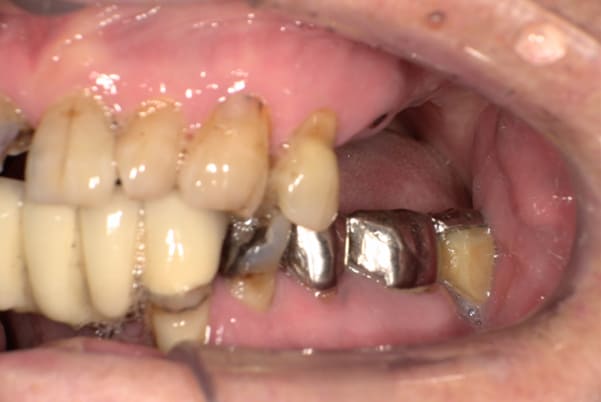

症例レポート[CASE.02]

- 男性(60代)

- 入れ歯がカパカパする、歯がぐらぐらして痛い、食いしばれない

- 上顎精密総金属床総入れ歯

- 下顎精密金属床部分入れ歯

上の前歯が重度歯周病により動揺し、残せない状態のため、入れ歯も動揺がありました。

バネをかける歯は繋げることで強度を増し、歯への負担を軽減し、歯の寿命を長くする設計へ。

バネがかかる歯の被せ物は、歯への負担を減らし、入れ歯が動きにくいようになる形態をあらかじめ付与することで、より入れ歯の機能が高まります。

治療を行う際、被せ物や入れ歯は、別々に考えるのではなく、一口腔単位としてお口全体のことを考え最良の治療計画を立てることが歯の寿命、機能効果を向上させるため、専門医としてこのことは常に心掛けて治療を行っています。

残りの歯に負担がかからないよう、被せ物と入れ歯の一体化を図った入れ歯

治療前は上下奥歯の入れ歯が削れていることで、かみ合わせが低くなり唇もつむった状態でした。

かみ合わせを適切な高さに戻したことで、本来の自然な口元へ。